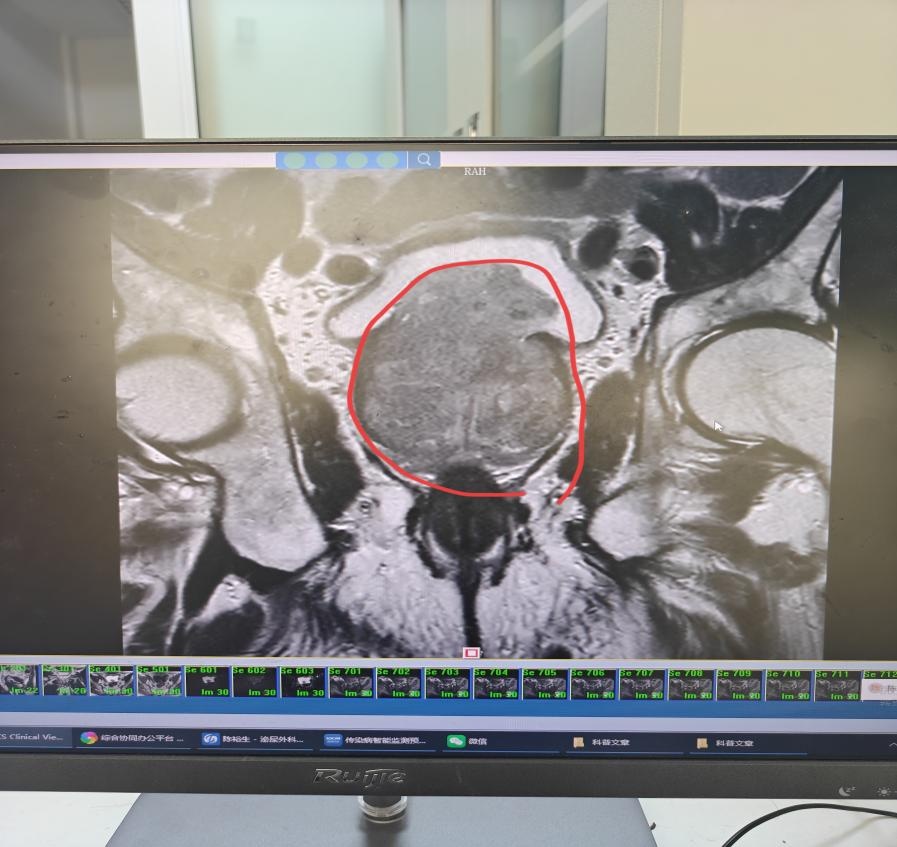

刘爷爷的情况更为棘手:不仅高龄,还合并高血压,既往有脑梗塞病史,长期服用阿司匹林,更关键的是,他的前列腺体积高达116g,相当于正常前列腺(约20g)的5倍多,手术难度和麻醉风险大幅增加。